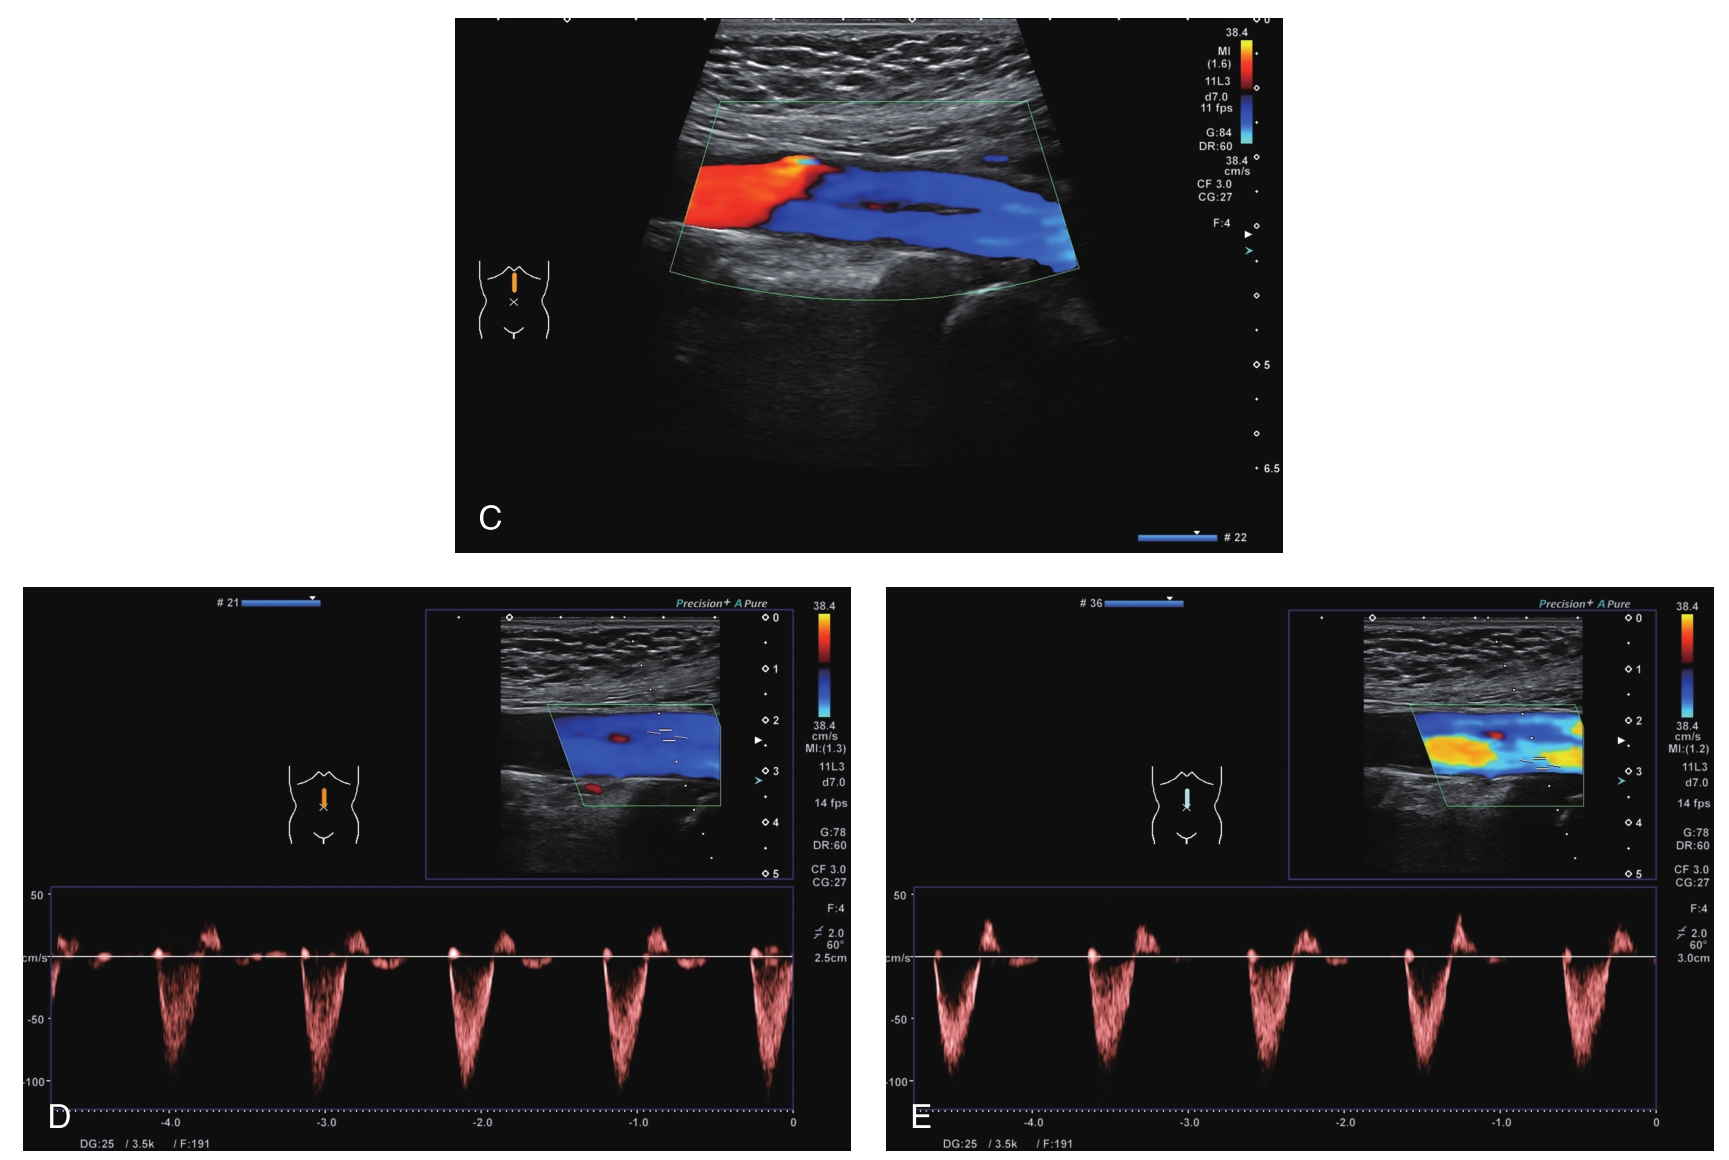

CDFI及脉冲多普勒超声表现见图9-1C、D、E。

图9-1 腹主动脉夹层动脉瘤超声图像

二维灰阶超声(A、B)示腹主动脉下段见漂浮线状高回声。CDFI(C)示真腔、假腔血流均充盈良好。脉冲多普勒超声(D、E)示真腔、假腔血流流速基本一致。